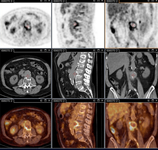

Q fever aortic mycotic lumbar aneurysm diagnosed at PET scan: 18F-fluorodeoxyglucose PET/CT. In this asymptomatic patient with heart valve history with elevated serology, the PET scan diagnosed an aortic endocarditis on native valve with thoracic and lumbar aortic mycotic aneurysms

Institut Hospitalo-Universitaire Méditerranée Infection (patient consent obtained)

Q fever aortic mycotic thoracic aneurysm diagnosed at PET scan: 18F-fluorodeoxyglucose PET/CT. In this asymptomatic patient with heart valve history with elevated serology, the PET scan diagnosed an aortic endocarditis on native valve with thoracic and lumbar aortic mycotic aneurysms